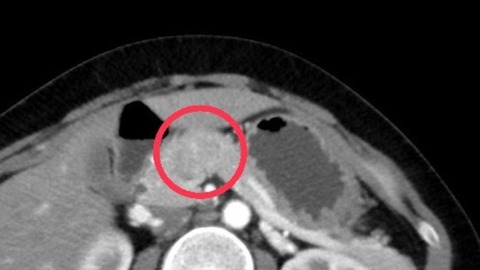

Hình ảnh chụp cắt lớp khối u tuyến tụy của người phụ nữ

Liên Tiểu Hồng, bác sĩ trưởng một phòng khám ở Đài Loan (Trung Quốc), đã chia sẻ trường hợp này trên mạng xã hội. Một phụ nữ 50 tuổi không hút thuốc hay uống rượu, không mắc bệnh mãn tính hay tiền sử gia đình, tuy nhiên gần đây, cô cảm thấy khó chịu và bụng luôn có cảm giác căng tức trong suốt 1 tháng qua. Thậm chí, cô còn đột nhiên sụt 9kg. Khi đi khám, kết quả nội soi dạ dày sơ bộ cho thấy dạ dày của cô "vỡ nhẹ". Nhưng siêu âm và chụp cắt lớp thêm cho thấy có một cái bóng dài 4cm trên tuyến tụy của người phụ nữ, vốn bị nghi ngờ là ung thư tuyến tụy.

Bác sĩ Liên Tiểu Hồng giải thích rằng chỉ số khối u của người phụ nữ "CA19-9 (kháng nguyên carbohydrate 19-9)" đạt hơn 200, gấp 7 lần giá trị bình thường, tức tương đương với bệnh đang ở giai đoạn giữa và cuối". Vì khối u khá lớn và gần với mạch máu, nếu không thể mạo hiểm phẫu thuật, bạn chỉ có thể sử dụng hóa trị trước, hy vọng khối u sẽ thu nhỏ lại.